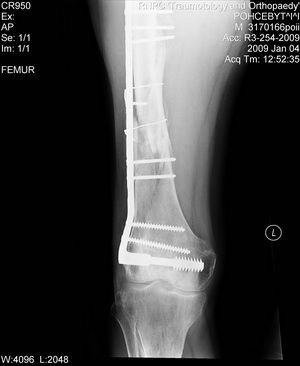

Больной 42 лет получил перелом проксимального отдела бедра. Ранее (1 год назад) оперирован

на том же бедре по поводу оскольчатого диафизарного перелома.

Четкой консолидации диафизарного перелома на рентгенограммах нет. Сопутствующие

заболевания - tbs и гепатит С. При обсуждении хотелось бы услышать варианты лечения 1) "в

идеале" и 2) с учетом социального статуса.